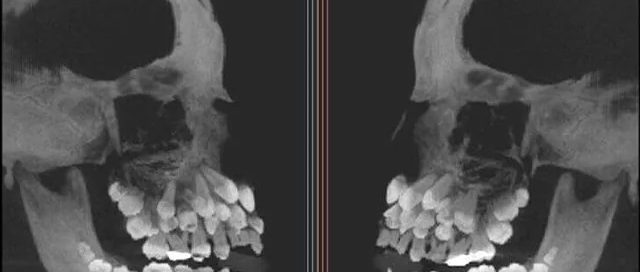

Dr Katsu Takahashi Hidden Third Set of Teeth